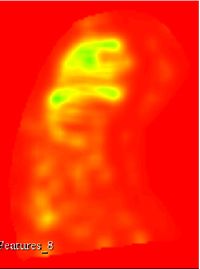

This extensions contain several modules that can be used to compute feature maps of N-Dimensional images using two well-known texture analysis methods: the study of Grey Level Co-occurrence Matrix (GLCM) and the study of Grey Level Run Length Matrix (GLRLM). The main algorithms used in this extension are part of a remote module of ITK called itkTextureFeatures Key Features:

Texture features

Texture feature maps

Run Length texture feature maps